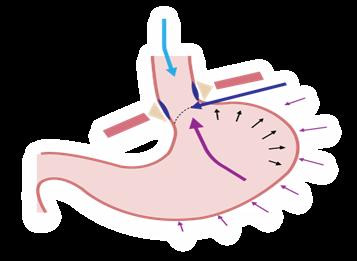

Se produce por un accidente de una placa vulnerable (ruptura) debido a que presenta una capa fibrosa delgada y núcleo lipídico grande. La exposición de colágeno activa la hemostasia, formándose un trombo que causa una oclusión aguda del flujo coronario y produce dos cuadros, según las alteraciones en el electrocardiograma (ECG).

Síndrome coronario agudo sin elevación del ST (SCASEST): cuando la placa trombótica provoca una oclusión parcial del flujo coronario y en el trombo predomina la agregación plaquetaria.

Síndrome coronario agudo con elevación del ST (SCACEST): cuando la placa trombótica produce una oclusión total del flujo coronario y en el trombo predomina la fibrina.